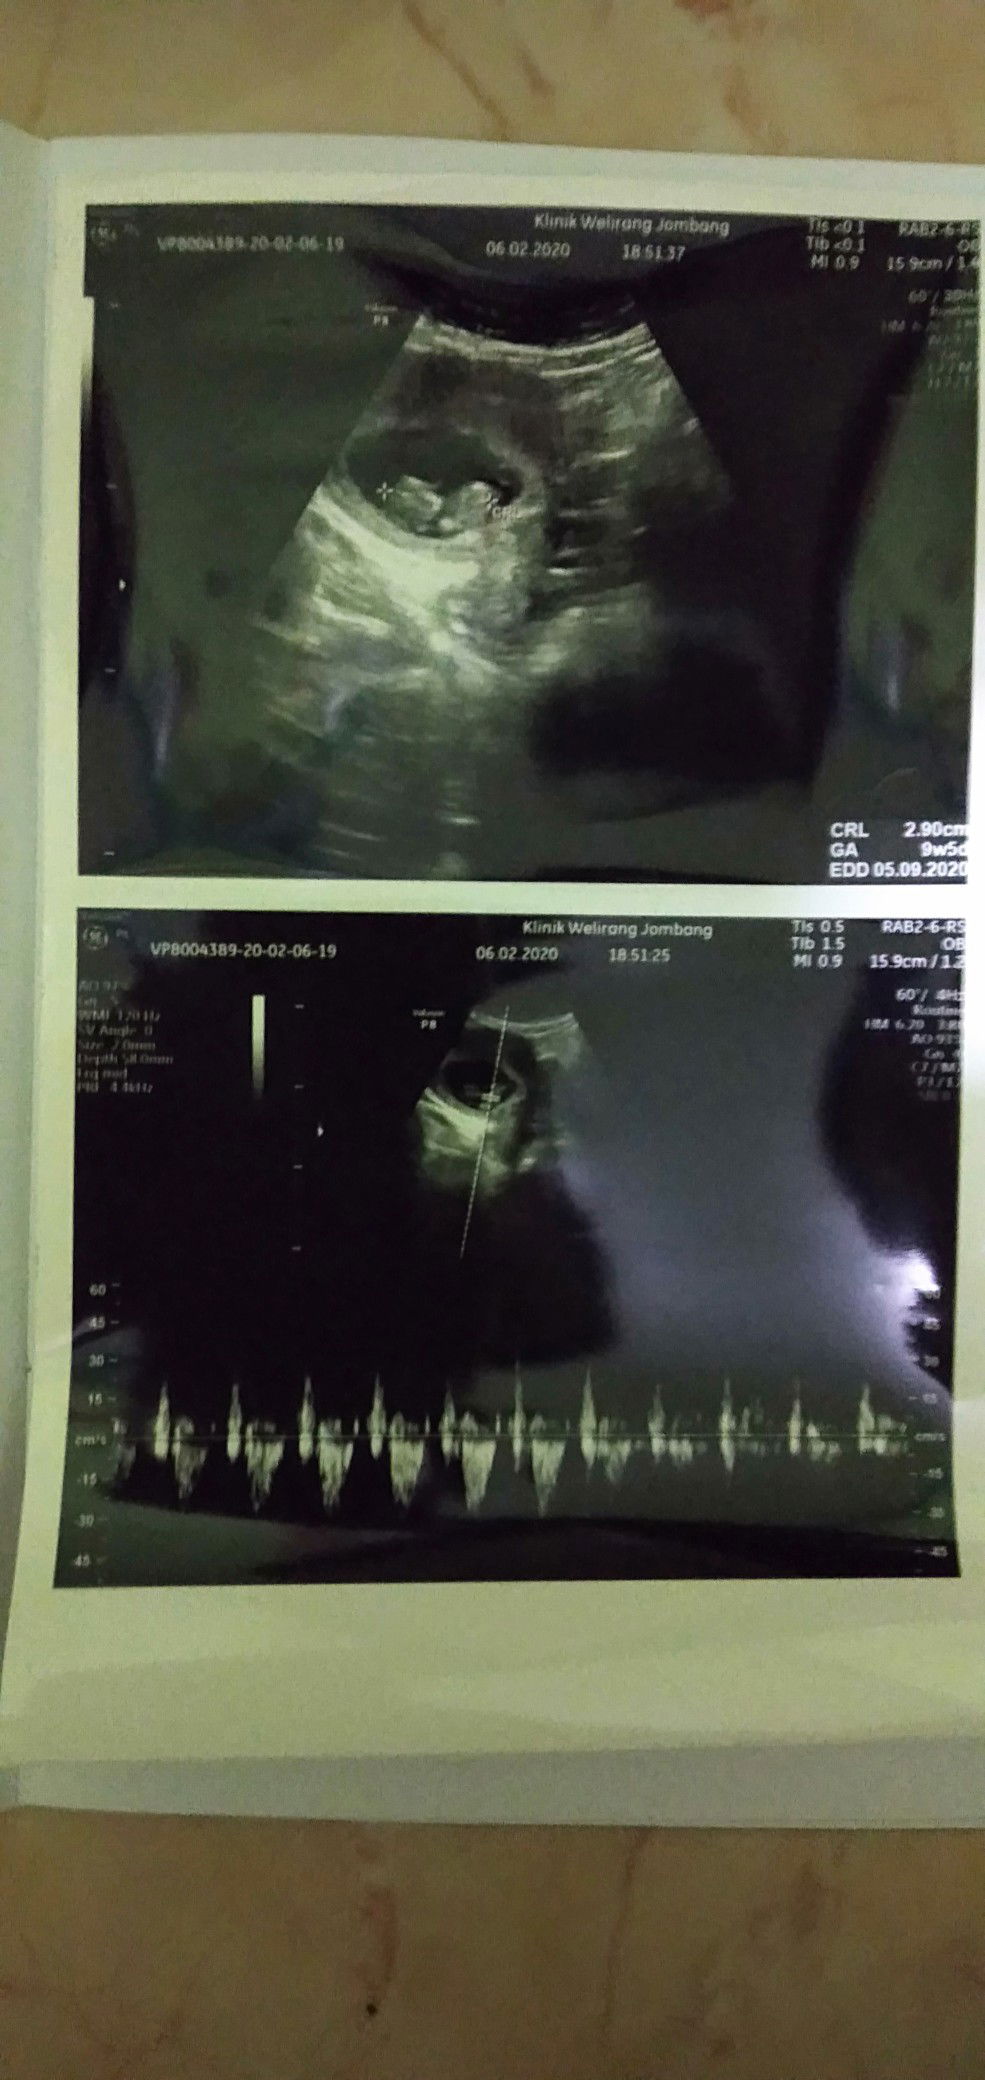

Alhamdulillah,bisa liat dek utunnya..sudah nampak ???

9minggu 3hari

maasya Allah..iya keliatan bun jd inget waktu hamil usia2 segitu seneng banget liat utunnya kayak lagi tiduran munggungin..padahal kyknya bukan gt deh yaa haha